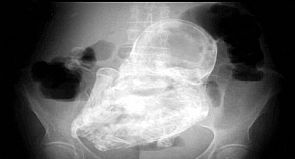

عمرها 82 وتحمل جنينا متحجرا عمره 40 عاما

أدخلت امرأة كولومبية تبلغ من العمر 82 عاماً المستشفى الاثنين الماضي وهي تعاني من آلام في أحشائها، حيث كانت تعاني من الإسهال.

غير أن ما اكتشفه الأطباء في مستشفى تونخويليتو في العاصمة بوغوتا أذهلهم بعد أن تبين أنها تعاني من حالة نادرة يطلق عليها اسم 'الجنين المتحجر'.

وتحدث هذه الظاهرة عندما يموت الجنين خلال الحمل خارج الرحم، لكنه يكون كبيراً بحيث لا يمكن للجسم أن يخرجه، ثم يصاب بالتكلس، أي يغطيه الكالسيوم.

وعلى الفور حول الأطباء المرأة العجوز إلى قسم الجراحة لإخراج الجنين المتحجر منذ ما يقرب الأربعين عاماً.